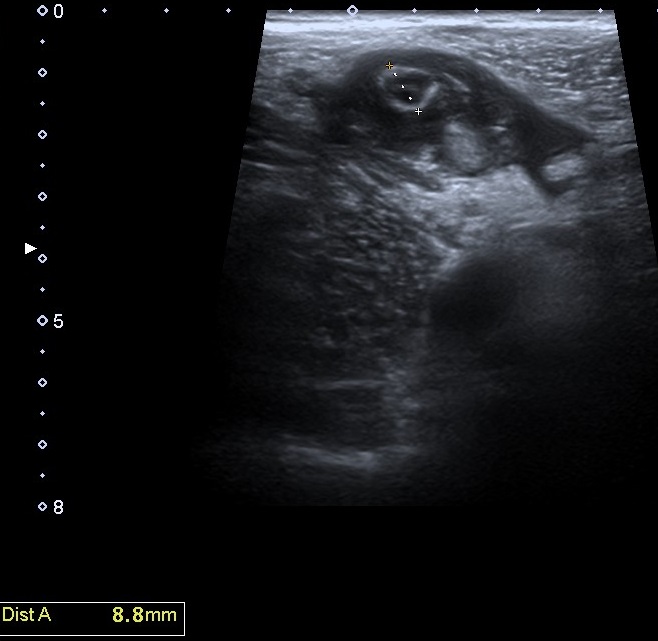

Se realiza una exploración abdominal ecográfica donde se observa hígado de ecogenicidad normal sin lesiones ocupantes de espacio. Vesícula biliar normal, vía biliar no dilatada. Ambos riñones de tamaño y aspecto normales. Páncreas, bazo y aorta normales. En fosa ilíaca derecha se observa apéndice cecal engrosado (imagen 1) con llamativa hiperecogenicidad de la grasa abdominal en relación con cambios inflamatorios (imagen 2). Colección abdominal en relación con cambios inflamatorios 3 x 3 x 5,3 cm (imagen 3).

La ecografía clínica se ha convertido en una herramienta útil para el diagnóstico temprano de apendicitis aguda. Gracias a su accesibilidad, permite realizar una evaluación rápida, ayudando a identificar signos como el engrosamiento del apéndice o la acumulación de líquido periapendicular.